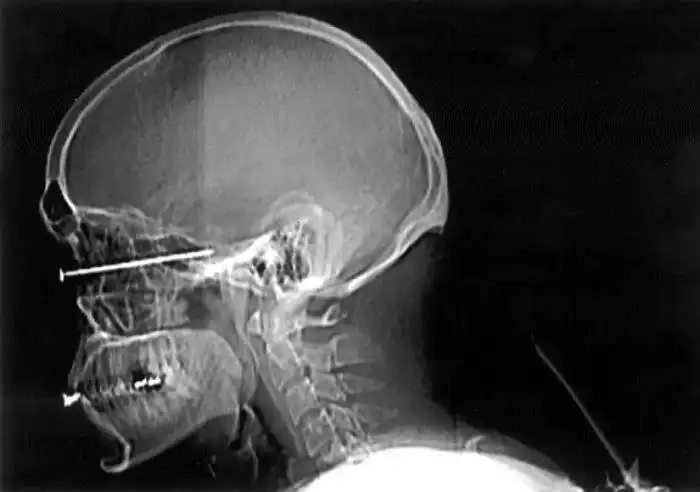

На рентгеновских снимках людей порой можно обнаружить самые необычные предметы, которые находятся в их теле.